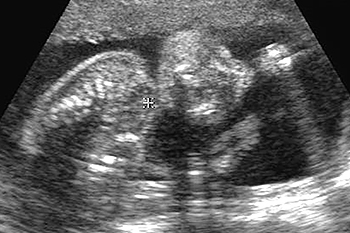

子宮の中にいる赤ちゃんの超音波写真を見てみましょう。

妊娠中の子宮は、丸くて柔らかく赤ちゃんが心地よく過ごせる場所です。赤ちゃんは本来胎内を、膝を曲げ、指をなめられる姿勢で過ごします。

ところが、子宮まわりの筋肉がコリ固まってカチカチだったり内臓が下がって子宮が押しつぶされたりすると、子宮が細長い形になってしまいます。この中の赤ちゃんは窮屈で楽な姿勢をとることができません。

胎内姿勢と生まれた後の関係

胎内での窮屈な姿勢は、生まれてからの向きぐせや体のゆがみ、コリにつながりやすくなります。また、膝が伸びた状態が妊娠後期まで続くと、股関節脱臼になりやすいという研究発表もあります。

子宮を横方向に撮影 10週6日